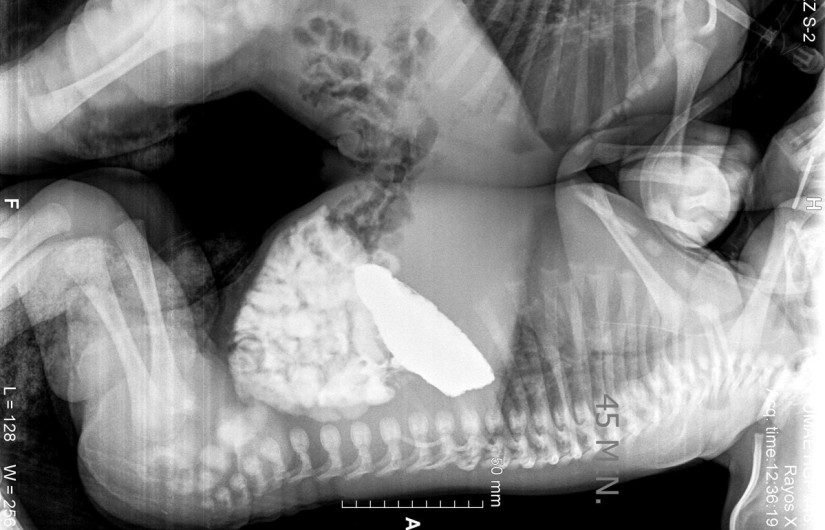

Médicos del Instituto Mexicano del Seguro Social (IMSS), en León, Guanajuato, separaron con éxito a siameses que permanecían unidos por el tórax y abdomen.

Los infantes nacieron por cesárea el año pasado 15 de diciembre, sin complicaciones, tras distintos exámenes de tomografía, ecocardiograma y resonancia magnética, fueron aptos para la cirugía de separación.

El equipo de cirujanos, iniciaron la incisión en la línea media que unía a los bebés y utilizando la técnica de electrocoagulación sin complicaciones, logrando separarlos con éxito.Después de permanecer en terapia intensiva, los pequeños fueron dados de alta, asistiendo el 2 de marzo a su primer cita con un buen estado de salud.